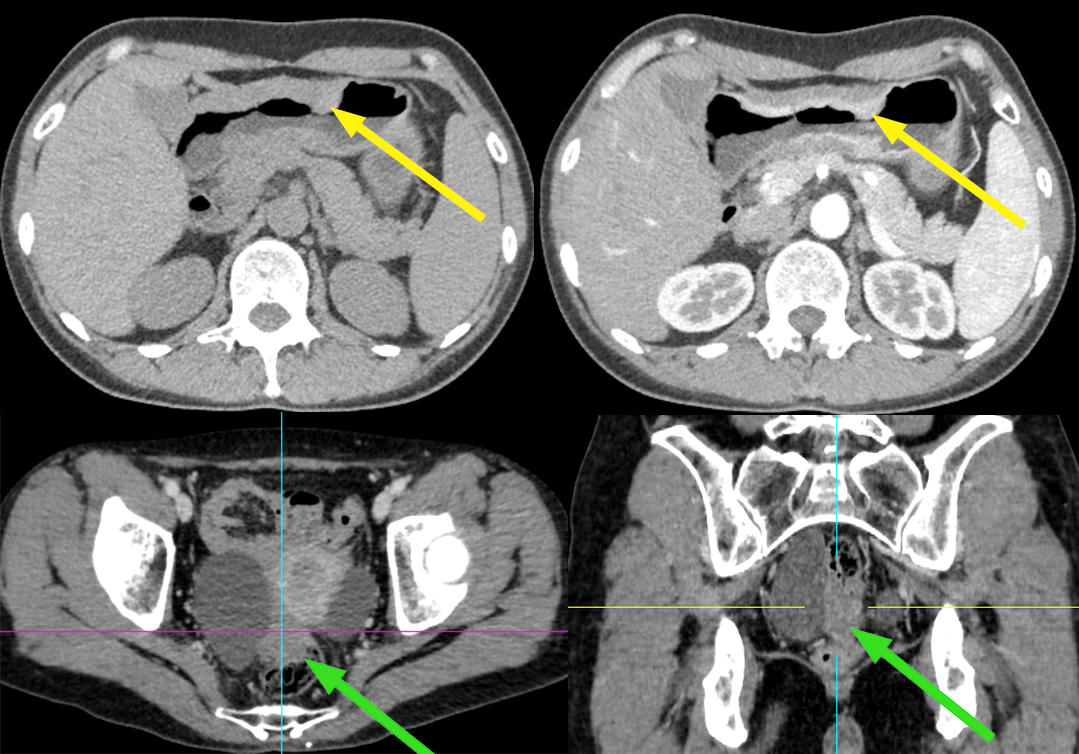

患者,女,70 岁,因排便习惯改变 1 年入院,肠镜及病理:升结肠近回盲部中低分化腺癌;CA125 正常。

【病例】盆腔肿块,需要考虑到这个来源…-2

影像描述:回盲部肠壁限局性环状增厚,突向腔内,表面不光滑,管腔明显变窄,浆膜层毛糙,增强呈明显不均匀强化,与肠壁边界不清,与周围组织分界尚清,周围脂肪间隙密度增高、浑浊,可见多个结节状软组织密度影,大小约 0.4-1.3 cm,明显强化。右侧附件区见较大囊实性团块影,其内可见分隔,大小约 6.7X5.5 cm,增强扫描实性部分及分隔可见明显强化,与邻近肠管及子宫体分界略欠清。

病例 2 手术:结肠癌合并卵巢转移癌